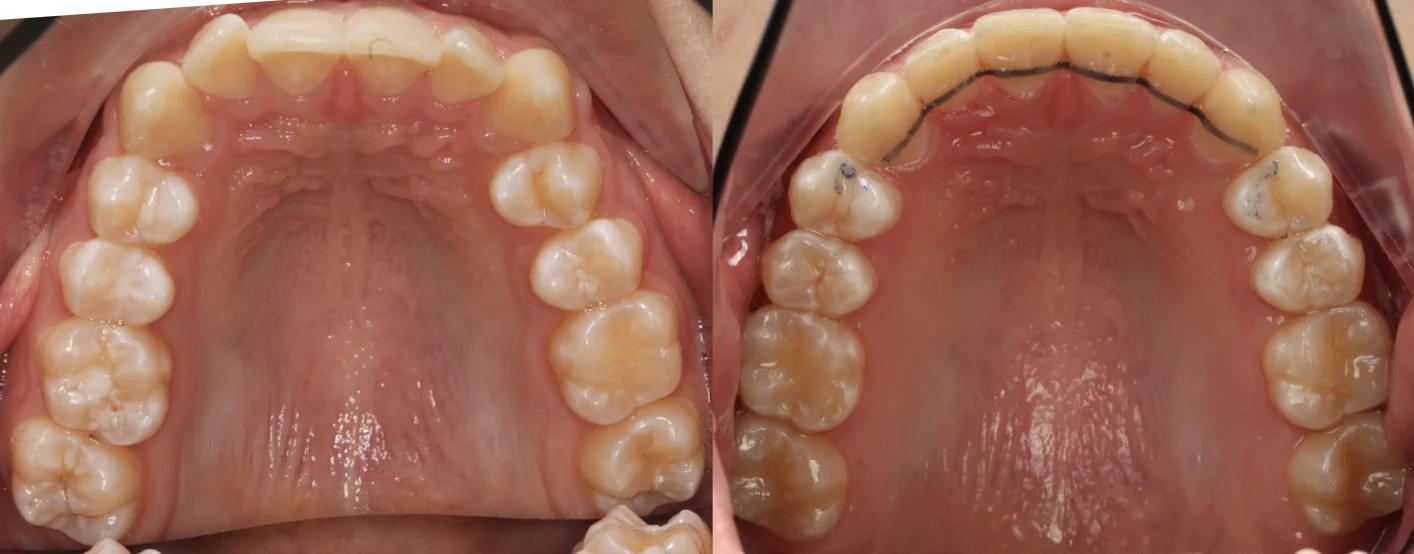

Нарушение соотношения челюстей и неправильное положение зубов — зубные ряды смыкались некорректно, зубы стояли со смещением.

Прозрачные элайнеры Invisalign на обе челюсти. Выровнять зубы и нормализовать смыкание. Срок — около 2 лет.

Решение: Поставили элайнеры Invisalign на обе челюсти. Лечение заняло 4 года — случай потребовал нескольких этапов коррекции, каждый из которых последовательно приближал зубы к нужному положению. Капы менялись каждые 1–2 недели, контрольные визиты — для отслеживания прогресса и выдачи новых наборов. Зубы встали на место, смыкание пришло в норму. Зафиксировали ретейнеры на обе челюсти, пациент направлен к ортопеду для завершающего этапа.

Случай потребовал нескольких последовательных этапов коррекции. Invisalign позволяет дозаказывать капы в рамках лечения, и здесь это понадобилось — каждый следующий этап доводил положение зубов точнее. Результат достигнут, прикус стабилен, ретейнеры на месте. Пациента направила к ортопеду.